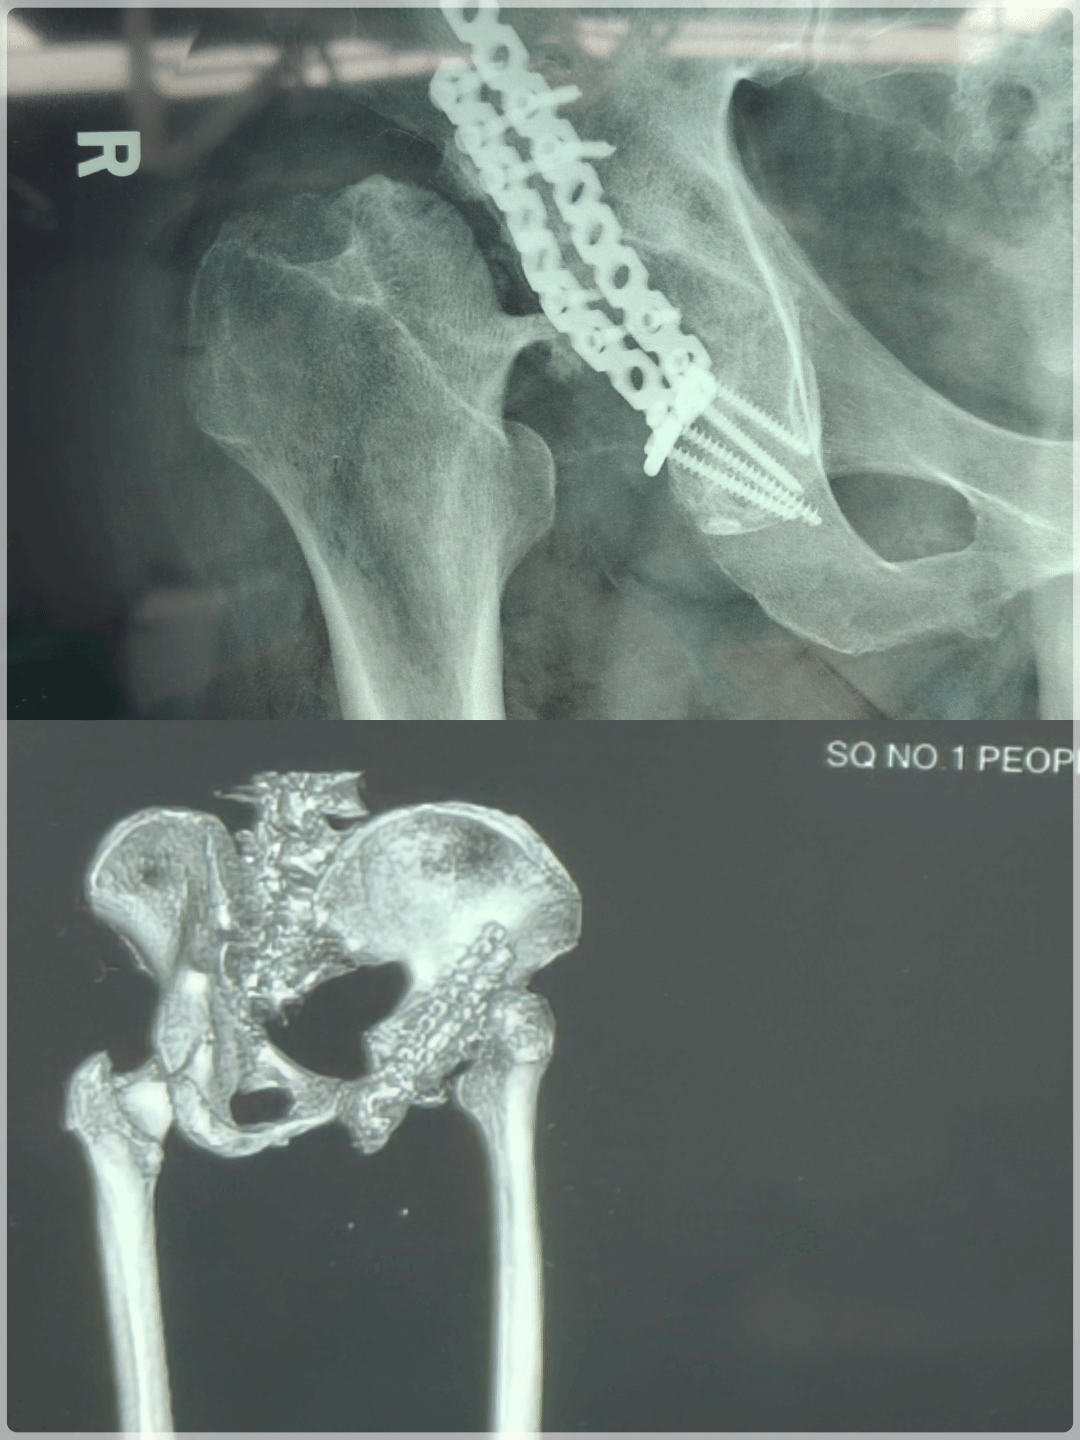

一年前,赵先生(化名)因髋臼骨折接受切开复位内固定手术,本以为伤痛就此终结,却在术后出现股骨头缺血性坏死、关节塌陷,髋关节活动严重受限,疼痛反复发作,日常行走极为困难。经外院专家推荐,慕名来到我院骨一关节外科寻求治疗。

(治疗前)

接诊后,骨一关节外科主任郭旗团队详细评估发现,赵先生病情极为复杂:既往骨折导致髋关节解剖结构严重畸变,局部骨质条件差,加之长期制动引发软组织粘连,为全髋关节置换带来巨大挑战。传统手术高度依赖医师经验,假体安放角度、深度、旋转中心难以精准把控,易出现双下肢不等长、假体松动、术后脱位等并发症,不仅影响关节功能,还会缩短假体使用寿命。